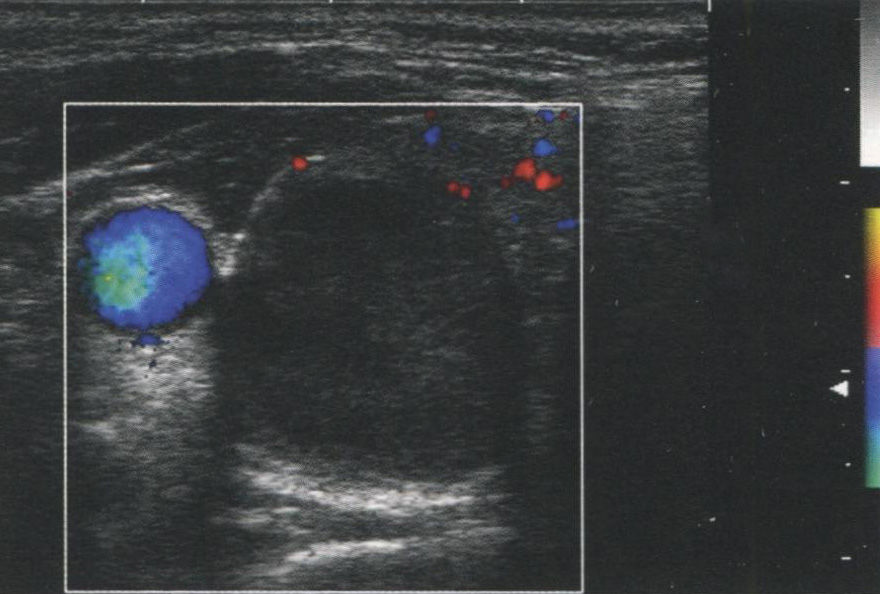

Рис. 3.4 демонстрирует фолликулярный рак в нижнем полюсе щитовидной железы (ЩЖ) с очень высоким уровнем кровотока. Визуализируется нижняя щитовидная артерия, кровоснабжающая узел. На рис. 3.5 показан узел, без значимой внутриузловой васкуляризации, лишь с немногочисленными сосудами на периферии. Этот узел — доброкачественная фолликулярная аденома.

Рис. 3.5. Аваскулярный узел. Доброкачественная фолликулярная аденома без внутриузлового кровотока